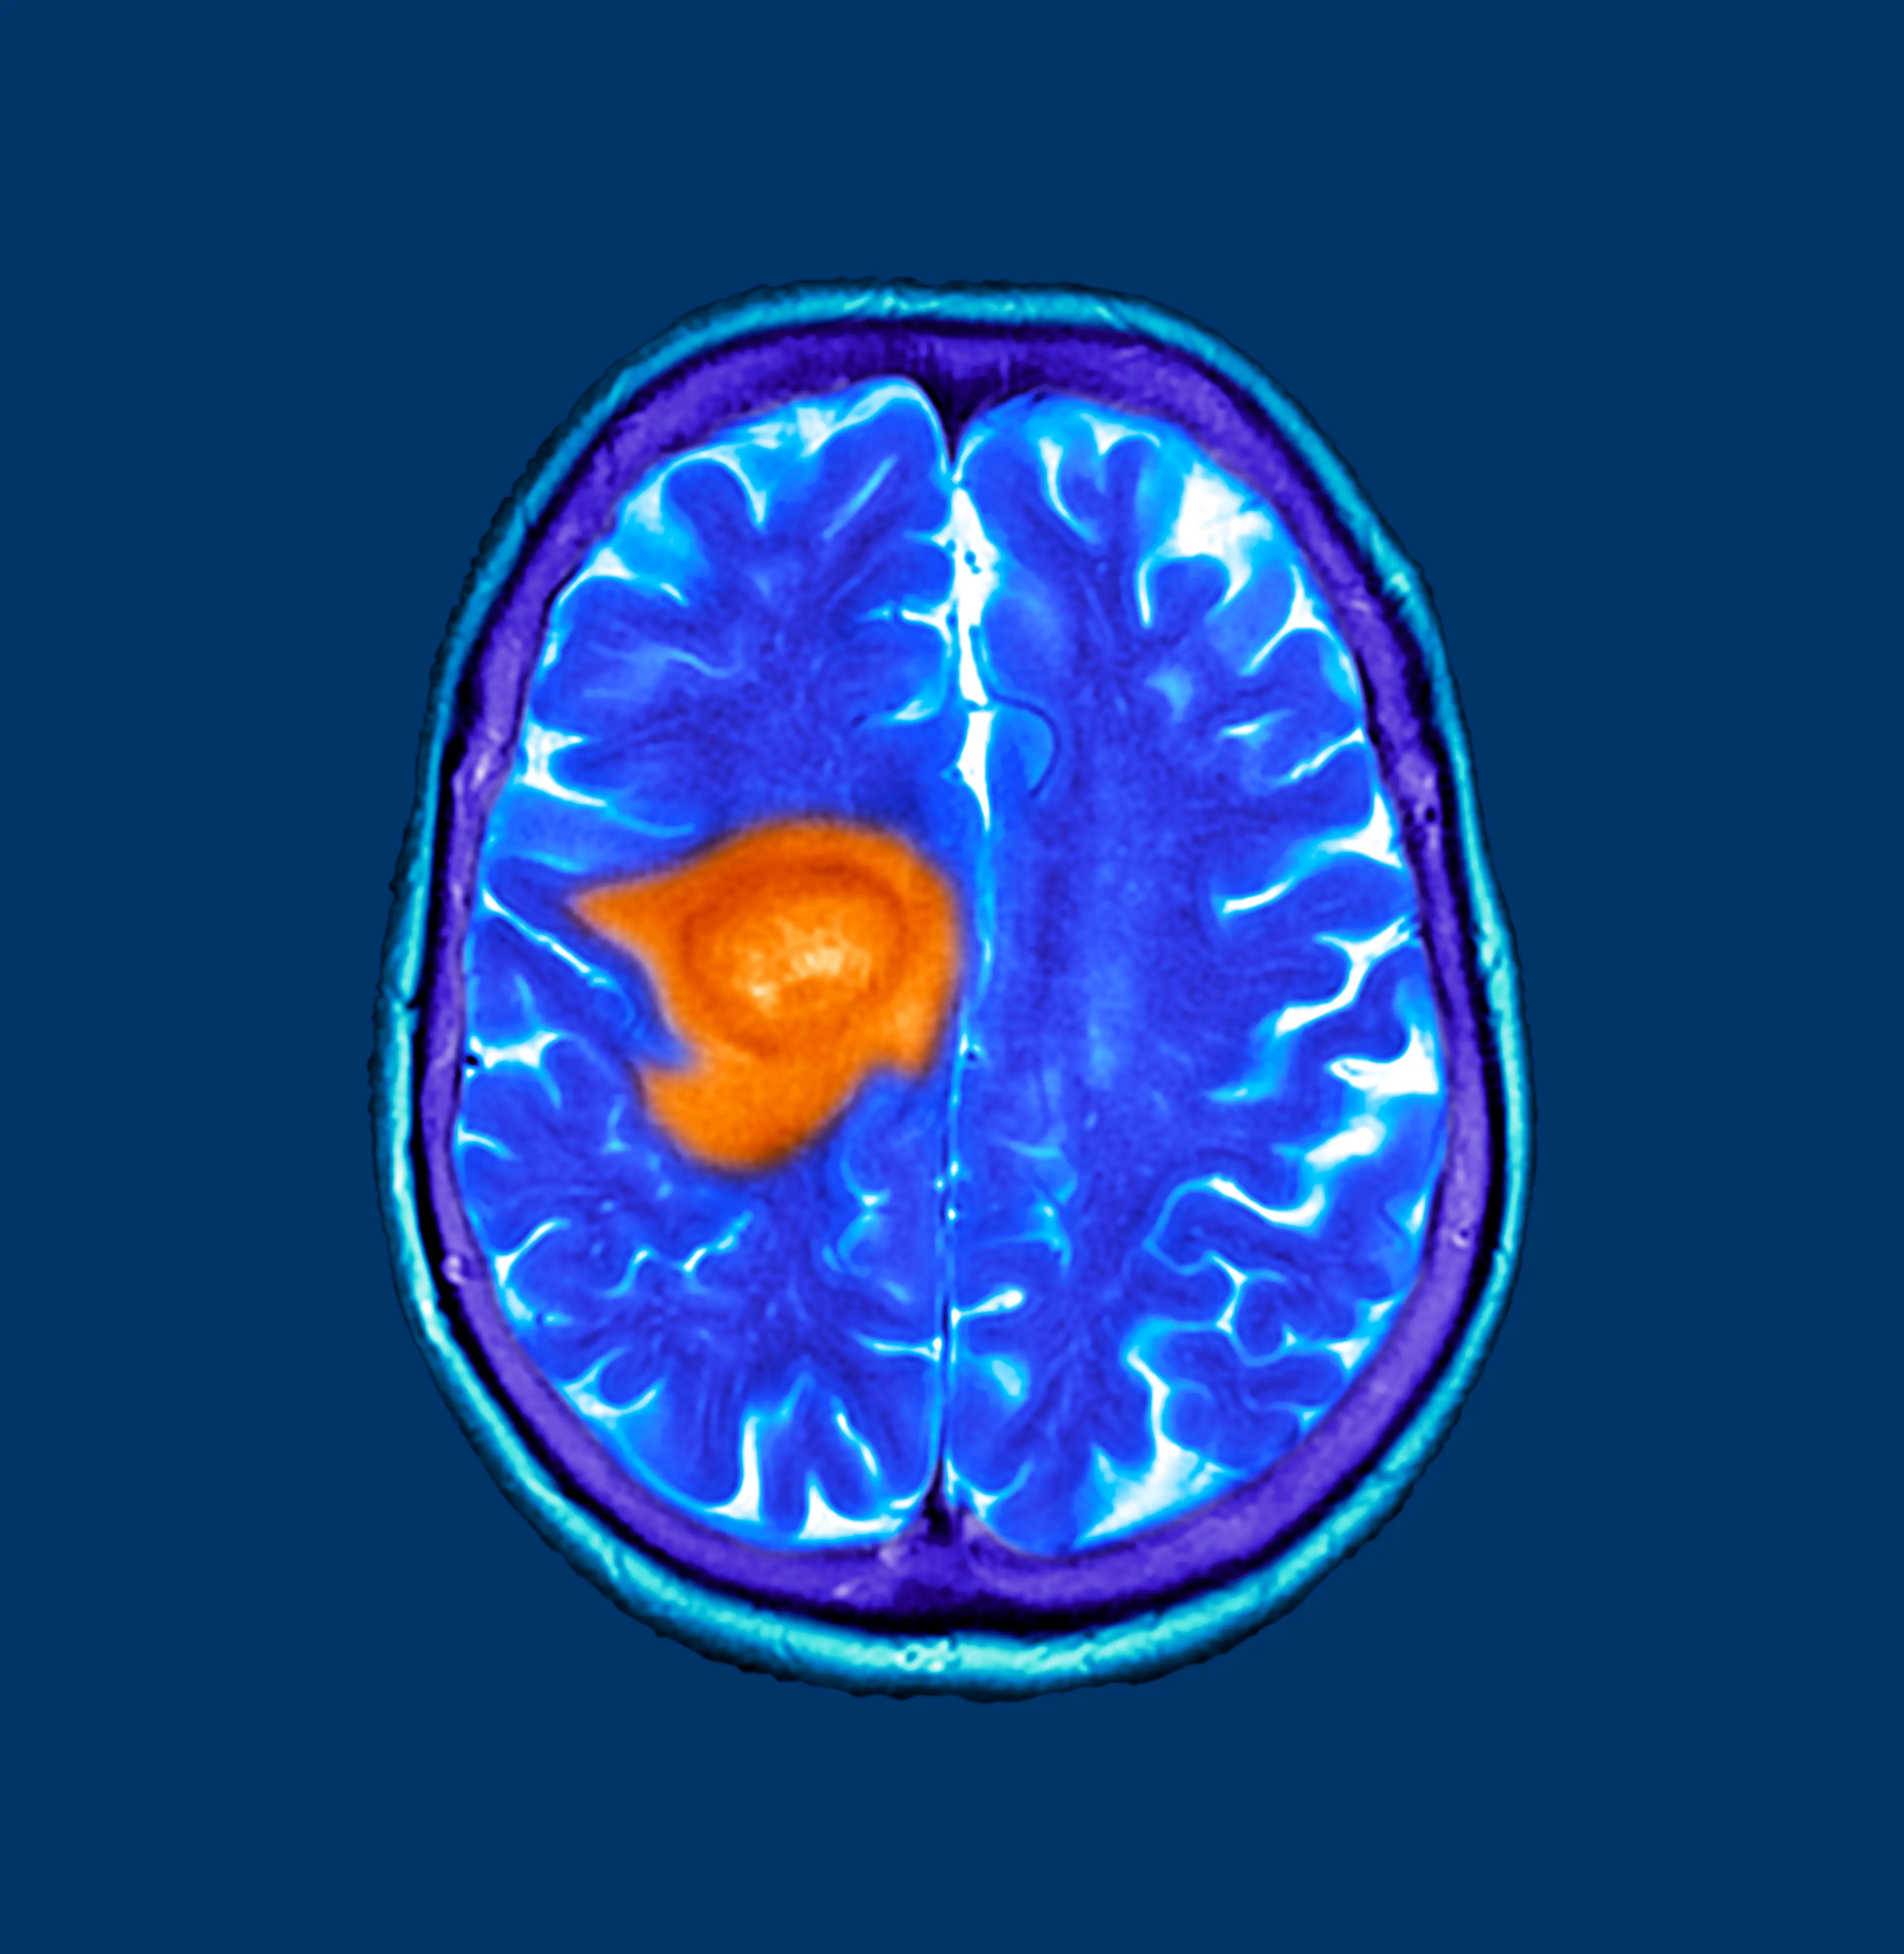

Experts have revealed that a very specific change in personality may be an early sign of rare brain cancer known as glioblastoma, which is a type of glioma.

Glioblastoma (GBM) is known as one of the most common, complex, treatment-resistant, and deadliest cancers that completely devastates the brain, which, as we know, controls cognition, mood, behaviour, and personality, as well as every function of each organ and body part.

The fast-growing cancer typically has a poor prognosis, with roughly just 25 percent of those diagnosed surviving for one year or more.

What are the symptoms of glioblastoma?

Now, according to Aaron Cohen-Gadol, MD, some of the most common symptoms of gliomas include personality changes and irritability.

Other symptoms include:

- Recurring headaches

- Drowsiness

- Unprovoked nausea and vomiting

- New-onset seizures

- Difficulty speaking

- Loss of balance

- Personality changes and irritability